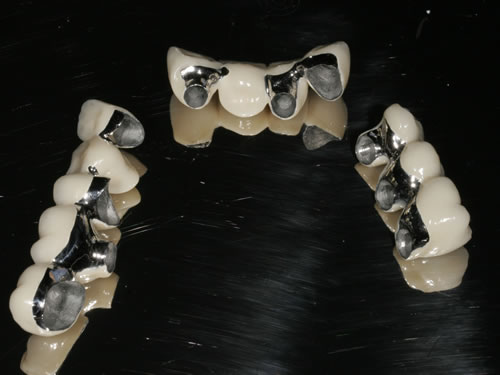

3.4 Reduzierte Bezahnung

Wenn viele Zähne fehlen und nur noch einige erhaltungswürdige Zähne vorhanden sind, die in den neuen Zahnersatz mit einbezogen werden können, dann spricht man von einer reduzierten Bezahnung. Die prothetische Versorgung wird als Hybridkonstruktion bezeichnet, da sie sowohl auf natürlichen Zähnen als auch auf Implantaten befestigt wird. Die Versorgung kann sowohl festsitzend - verschraubt oder zementiert - gestaltet werden (Abb. 3.24, 3.25), aber auch herausnehmbar, wobei dann häufig teleskopierende Konzepte verwendet werden (Abb. 3.26, 3.27).

Abb. 3.24: Festsitzende Hybridbrücke auf 4 Zähnen und 6 Implantaten.

Abb. 3.25: Brücken vor der Eingliederung.

Abb. 3.26: Hybridversorgung einer reduzierten Oberkieferbezahnung auf 4 Zähnen und 3 Implantaten.

Abb. 3.27: Ansicht des gaumenfreien, herausnehmbaren Zahnersatzes.